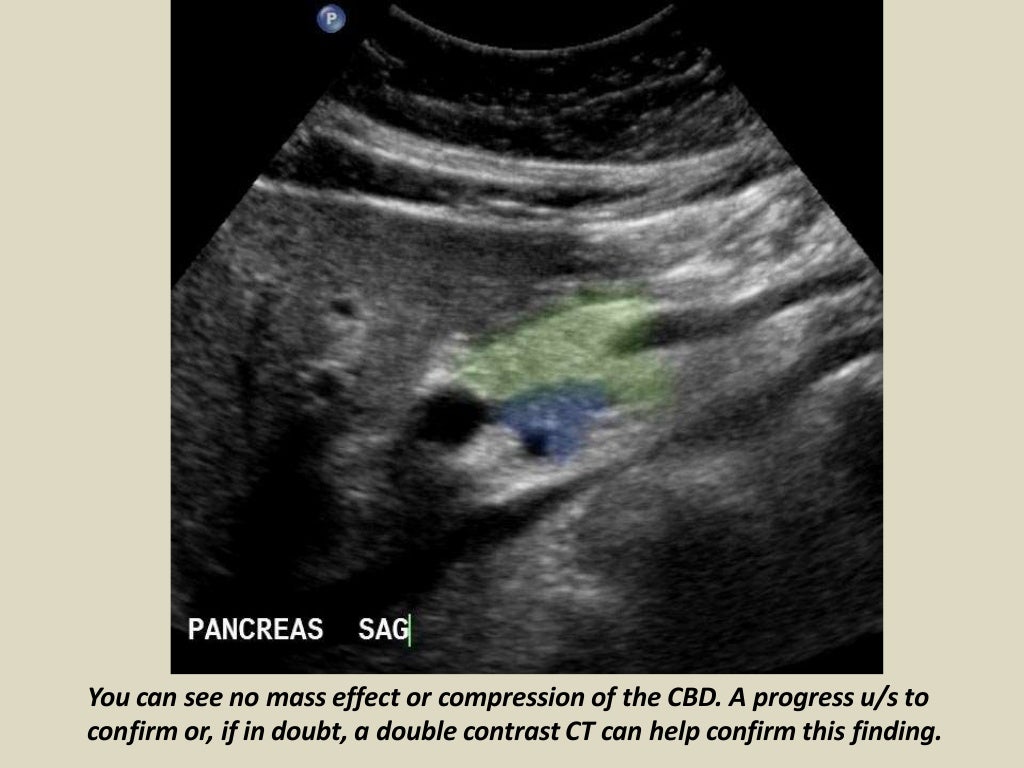

Ultrasound Upper Abdomen Showing Flow In Common Bile Duct Before And Abs Ultrasound These organs include the gallbladder, kidneys, liver, pancreas, and spleen. The kidneys, liver, gallbladder, bile ducts, spleen, and abdominal blood vessels can all be seen with an abdominal ultrasound. This is a specialised procedure that uses sound waves to obtain information about the structure and functions of the different organs within the body. an abdominal ultrasound can help evaluate. Abs Ultrasound.